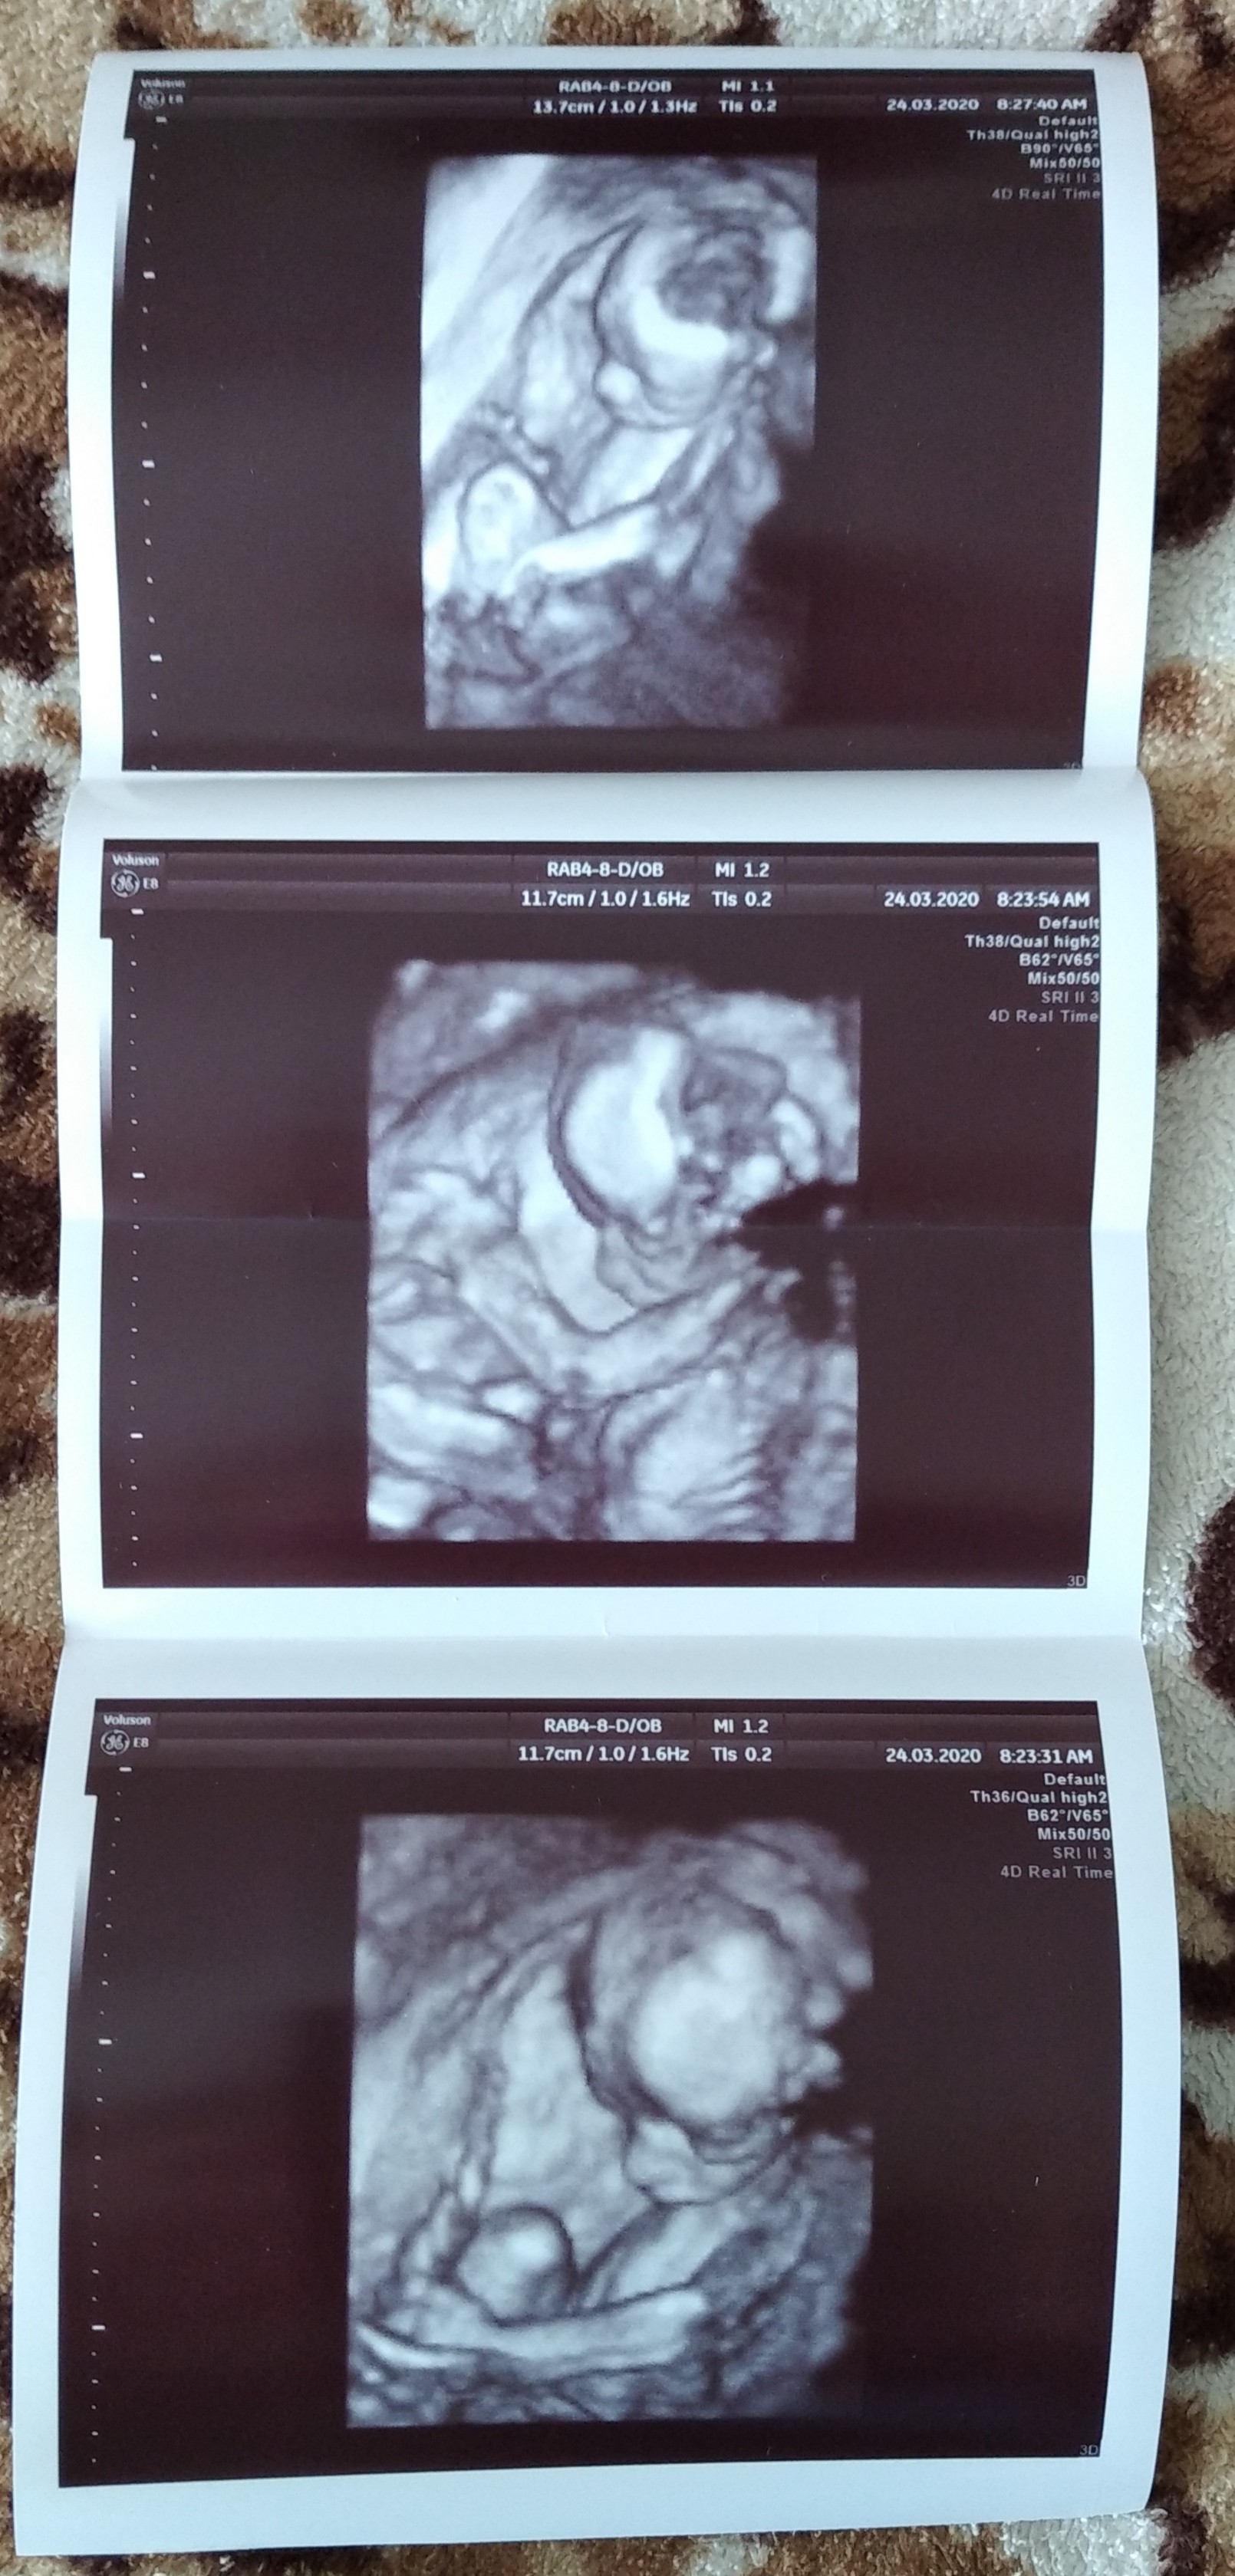

Ja też już po badaniu, fajnie że bez kolejek, każdy na godzinę, chyba pierwszy raz tak szybko wyszłam od lekarza 😅 Nasz Marcelek ma się dobrze, wierci się bardzo, chyba mu zimny żel na brzuchu nie odpowiadał 😉 21 tygodni 411g szczęścia🥰

Jest i on 🤭 pierwsze na monitorze co się pojawiło to sisiorek 😁 czyli w 21t5d mamy 420g synusia 100%. Nasz Piotruś 💕

Wstawiłabym jakieś foto ale z 4 zdjęć które dostałam na pendrive (kazał zabrać, bo bez męża oczywiście wchodziłam i myślałam że bicie serca będzie chociaż czy coś... Zawiedziona jestem) na jednym widać klejnoty, a na trzech nie wiem nawet co 😶

Lepsze ustrzeliła 3tyg temu moja gin, które mam na profilowym.